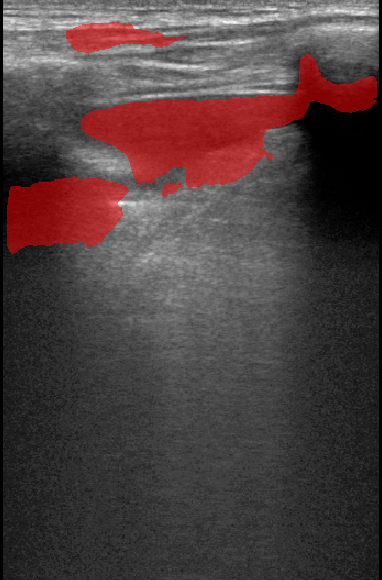

A total of 143 images were acquired from 59 patients. The images were obtained at the left and right PLAPS (PosteroLateral Alveolar and/or Pleural Syndrome) and subcostal views [4] with linear array and curved array (abdominal) ultrasound probes. The data were split according to the use of these probes into two datasets of 51 and 92 images, respectively for linear array and curved array. We denote these datasets as Dataset A (linear array) and Dataset B (curved array). All images were annotated at the time of acquisition to measure the extent of the effusion. These annotations consisted of small crosses at the top and bottom of the deepest area of effusion. See Figure 1 (left column) for example images.

Before being used for training and evaluating the models, each image was automatically cropped using a rectangular/cone mask to remove non-imaging content. Next, we applied an inpainting text algorithm using keras-ocr followed by template matching and edge detection algorithms from opencv to remove the annotations that were added to the images to measure the effusion. Examples of the outputs of this preprocessing are shown in Figure 1 (centre column).

All images in both datasets were manually segmented using the ITK-SNAP software [14] (www.itksnap.org) by a trained observer. Examples of ground truth segmentations are shown in Figure 1 (right column). These segmentations acted as ground truths for training and evaluating the proposed models. Additionally, a second trained observer performed independent segmentations of subsets of 10 random images each from the two datasets. These were used to compute an estimate of inter-observer variability in the manual segmentation process.

Qualitative prediction results of the two proposed models (baseline nnU-Net and nnU-Net with coordinate convolutions) on the two datasets are shown in Figure 2. Tables 1 and 2 summarise the quantitative performances in terms of DSC and area statistics. Histograms of the DSC values are shown in Figure 3. The median DSCs between the manual segmentations on the subsets of 10 images (i.e. the estimates of inter-observer variability) are also shown in Table 1.

It can be seen that, despite having fewer images, the baseline model for Dataset A obtained a higher median DSC than the model for Dataset B. For Dataset A the coordinate convolution model improved the DSC and reduced the area error and bias. In two-tailed Wilcoxon signed rank tests (0.05 significance) the difference between the baseline DSC and that of the coordinate convolution model was found to be statistically significant for Dataset A () but there was no statistically significant difference for Dataset B (). Interestingly, for both Dataset A and Dataset B, both the baseline and coordinate convolution models performed better than the estimate of inter-observer variability. However, we note that the inter-observer variability is quite high (i.e. median DSCs of 0.78 and 0.71), likely reflecting the difficulty and partly subjective nature of the effusion segmentation task. Therefore, it seems likely that the deep learning models are learning to segment effusion in the style of the main observer, which may not always be consistent with the second observer. In addition, the histograms shown in Figure 3 suggest that there are a significant number of failure cases in the outputs of both models (although fewer for the coordinate convolution model for Dataset A), again reflecting the difficulty of the task.

Rows 1-2: Dataset A. Rows 3-4: Dataset B.